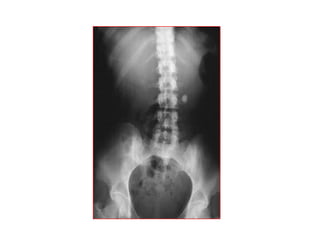

KUB BÌNH THÖÔØNG

 Thaáy ñöôïc caùc cô quan sau:

o Gan: thaáy ñöôïc bôø sau bôûi lôùp môõ sau phuùc maïc

o Laùch: coù theå thaáy ñöôïc

o Thaän: coù theå thaáy khoâng hoaøn toaøn

o Cô Psoas: bôø thöôøng thaáy roõ

o Daûi môõ caän phuùc maïc

 Nhöõng caáu truùc naøy khoâng phaûi luoân thaáy roõ

KHÍ BÌNH THÖÔØNG TRONG XQ

BUÏNG KHOÂNG SÖÛA SOAÏN

• Hôi trong daï daøy – taù traøng

• Ít hôi trong ruoät non

• Hôi trong ñaïi traøng goùc laùch, goùc gan, tröïc traøng

• Ít hôi laám chaám vuøng manh traøng

Phân bố hơi bình thường trong ổ bụng: túi

hơi DD, vài bóng hơi nhỏ trong RN, phân -

hơi trong ĐT.